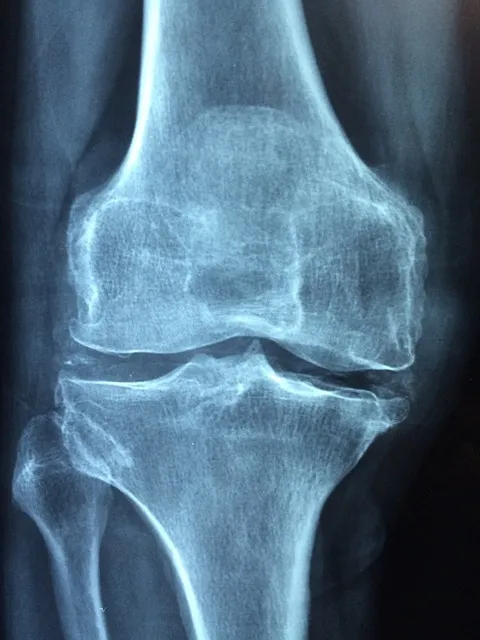

영상 검사

X-레이, MRI, CT 스캔 등의 영상 검사를 통해 무릎 관절 내 구조를 자세히 살펴볼 수 있습니다. 이를 통해 연골 손상, 인대 손상, 관절염 등의 상태를 진단할 수 있습니다.